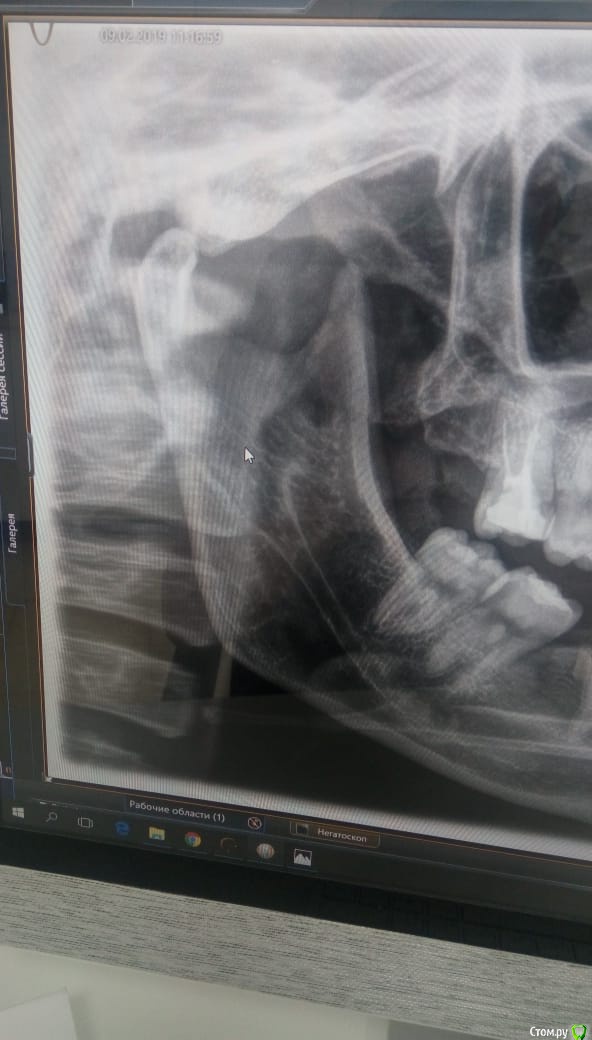

Daniyar Опубликовано 12 февраля, 2019 Поделиться Опубликовано 12 февраля, 2019 FYI 4 Ссылка на комментарий

Jurai Опубликовано 12 февраля, 2019 Поделиться Опубликовано 12 февраля, 2019 сколько времени прошло после вмешательства - на финальном снимке? Ссылка на комментарий

Daniyar Опубликовано 12 февраля, 2019 Поделиться Опубликовано 12 февраля, 2019 сколько времени прошло после вмешательства - на финальном снимке?09/02/19 Ссылка на комментарий